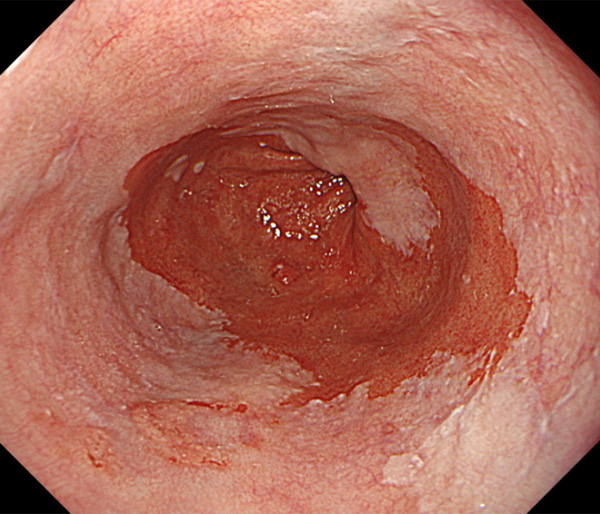

内視鏡所見と病理組織像の1対1対応が可能な症例を公募いたします。主にLSBEに発生した早期癌(HGDを含む)を対象としますが、興味深い症例であればSSBE癌でも結構です。採否は世話人へご一任ください。

症例呈示希望者は応募用紙に記入の上、代表的な内視鏡(2枚)、切除標本(新鮮、固定)、切り出し図、マッピング、代表的組織像とともに、Barrett 食道研究会事務局 barrett.shinshu@gmail.comへお申し込み下さい(10MB以下でお願い致します)。

特に、本邦では極めて稀なlong segment Barrett’s esophagus(LSBE)から発生した早期癌は、診断に難渋する場合も多く、欧米ではランダム生検による検出が標準的とされています。背景のBarrett食道もろとも全体を内視鏡切除+ラジオ波焼灼する欧米と異なり、ESDで内視鏡的な局所切除が基本の本邦では、存在診断+範囲診断(特に水平)を的確に行うことが不可欠です。

そのためには、一流の病理医による組織学的診断とエキスパート内視鏡医による拡大内視鏡像との一対一対応を徹底的に行うことで、『本来、見えないであろう拡大所見の先にある組織構築像が診えてくる』所まで内視鏡診断レベルを上げていく必要があります。その実現には、一対一対応を追究した症例(特にLSBE発生例)1例でも多く経験するしかありません。本研究会でBarrett食道腺癌(LSBE発生早期病変)を共に学び、拡大内視鏡像の一歩先を診るスキルを習得しましょう!一人でも多くの皆様のご参加をお待ちしています。

2026年1月24日開催の第19回研究会でご提示した検討症例です。 (画像をクリックすると拡大します)